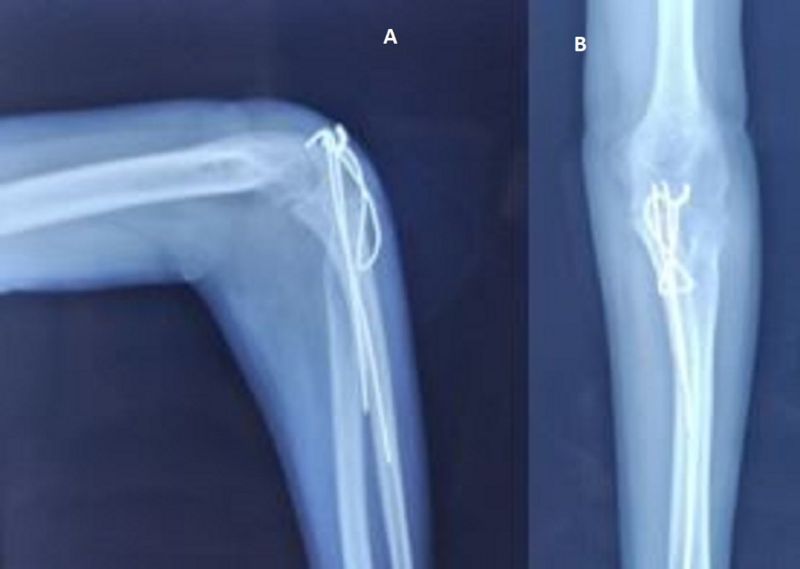

The patient was placed in a lateral recumbent position with the elbow placed on a support. A midline paratricipital posterior approach was used. The ulnar nerve was isolated, the elbow joint was approached from lateral and medial sides with triceps sparing. The olecranon fossa and trochlear notch contained fibrous tissues which were removed, arthrolysis was performed and the articular surfaces presented no irregularities. We then performed a triceps lengthening V-Y plasty which allowed us to achieve a congruent reduction of the articulation. We then used an olecrano-humeral K-wire to maintain stability in a 90° flexion position and proceeded to transpose the ulnar nerve anteriorly. The wound was then closed over a suction drain and the limb was immobilised for 15 days post operatively with a posterior slab. Passive mobilisation was started at 15 days after the removal of the K-wire.(Figure 6)

Figure 6: Post op X ray showing congruent elbow joint stabilised by a K wire